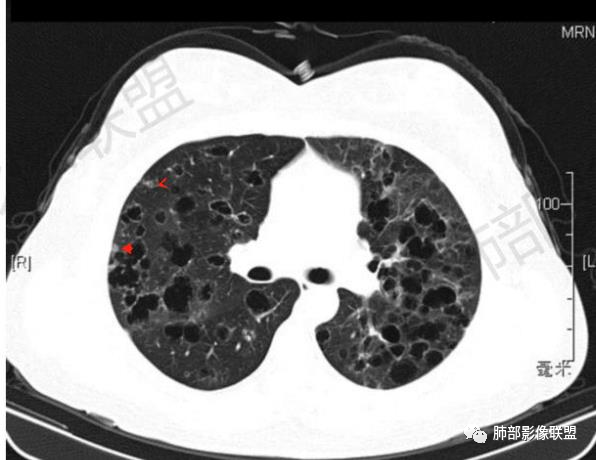

影像:双肺散在囊性病变,不规则,壁厚,部分见结节

晨读:女,31,间断咳嗽、咳痰9月。卵巢交界性囊腺瘤术后。胸部CT:双肺多发大小不等薄壁囊腔影,部分融合,形态不规则,个别囊壁偏厚。右肺上叶及左肺下叶纤维索条影。左下叶不规则囊腔影,壁不均匀增厚,周围不规则实性成分加GGO,放射性毛刺,胸膜牵拉。考虑:囊腔型Ca?转移?鉴别PLCH,Lam,LIp,BHD,CF,CPAM等,听大咖解析。

胸部CT:两肺多发囊腔,中上肺受累为主,囊腔形态不规则(囊有点丑),分叶状,囊壁厚薄不均,大部分囊壁薄。尚有一些结节影。

5.囊腔型肺转移瘤:常见于头颈部的鳞状上皮癌、胃肠道的腺癌、女性生殖系统肿瘤、肺外肉瘤的转移。

晨读病例有妇科肿瘤手术史,肺内病变转移瘤可能性大(而且一般盆腔肿瘤手术前基本都会完善胸部X检查,能够顺利完成手术估计手术时肺内无明显病灶),但肺囊肿有较明显的融合,这在转移瘤中较少见。综合上述考虑囊腔型肺转移瘤,鉴别PLCH。

病理结果:肺粘液腺癌(转移不除外)

盆腔肿瘤病理复检结果为:交界性粘液性肿瘤